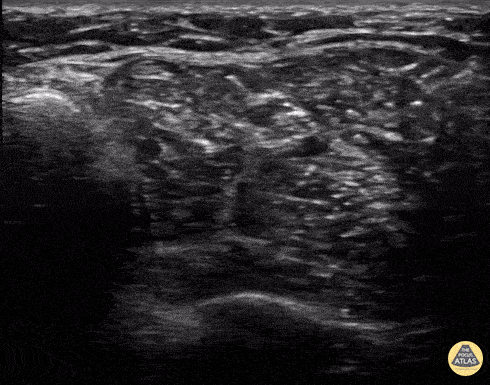

10 year old came in with laceration to the sole of the foot and likely retained foreign body after stepping on broken glass. A posterior tibial nerve block with ultrasound guidance was performed to provide local anesthesia. This is performed slightly superior to the ankle (where the nerve was best viewed in the patient), using in plane technique with a posterior needle approach. Demonstrated here is the tibial artery/vein dyad, with the tibial nerve located just to the right on the image seen, as hydro-dissection of the nerve is being performed with lidocaine to instill local anesthesia directly deep and adjacent to the nerve. The distal tibia is viewed as the hyperechoic structure deep on the screen. Contributor: Allie Grither, MD, St. Louis Children's Hospital (Washington University in St. Louis), @AGPemMD